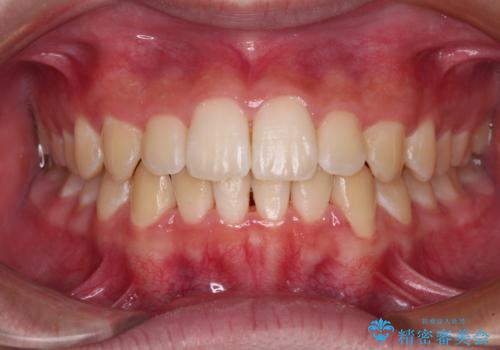

矯正歯科治療 → 叢生(でこぼこ・八重歯)

沖縄から飛行機で通院 インビザラインによる矯正治療

上顎の八重歯と下顎前歯の欠損 ワイヤー装置による抜歯矯正

気になる前歯を治したい インビザラインで気づかれずに矯正治療

八重歯で正中が右にずれている ワイヤー装置での抜歯矯正で正中位置を改善

しっかり使って短期間で治療 インビザラインによる叢生解消

八重歯がスッキリ 抜歯ワイヤー矯正

八重歯が気になる ワイヤーによる抜歯矯正できれいな歯並びへ

八重歯・前歯のがたつき 抜かない矯正 インビザラインで